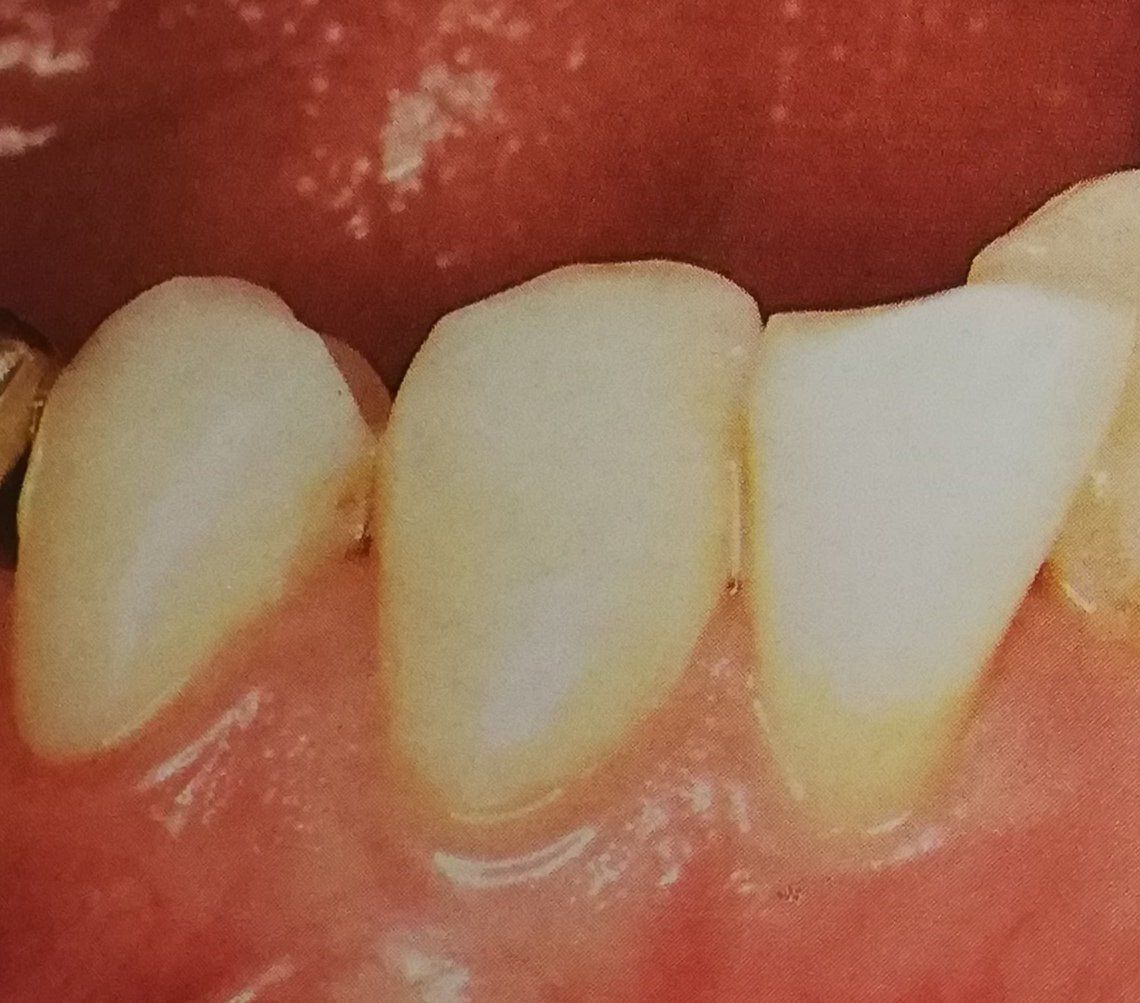

L'odontoiatria conservativa è finalizzata principalmente alla cura della carie dentale. L'obiettivo finale è quello di conservare l’elemento dentario compromesso ripristinandone la forma e il colore originario, per ottenere ciò ci si può avvalere sia di restauri diretti che indiretti.

- L’odontoiatria conservativa si concentra sulla rimozione della carie e sul ripristino della parte esterna del dente tramite otturazioni o ricostruzioni estetiche.

Spesso, le due discipline si completano: dopo una devitalizzazione, la parte visibile del dente viene ricostruita con materiali estetici per ripristinare funzionalità e armonia del sorriso.